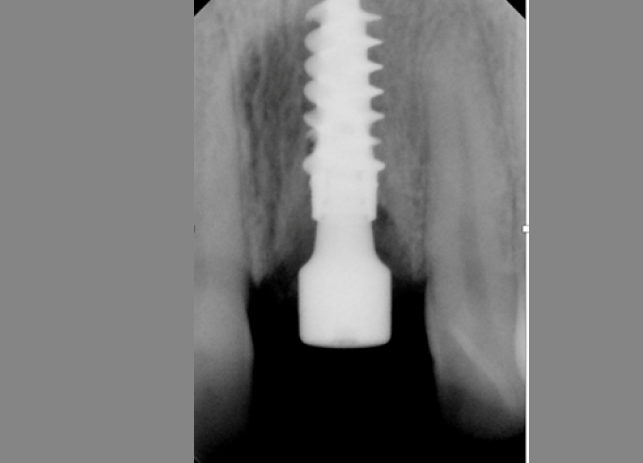

Рис. 15 Работа с уровня имплантата с имплантатами с внутренним соединением осложняется отсутствием параллельности соседних зубов

Множественные имплантаты редко располагаются параллельно, что затрудняет использование супраструктуры для имплантатов, установленных на уровне кости. Обычно абатменты размещаются ниже уровня мягких тканей, к ним трудно получить доступ. Существуют винтовые и мостовидные абатменты, которые можно использовать на уровне имплантата, но их использование может способствовать смещению костного гребня и потере кости.